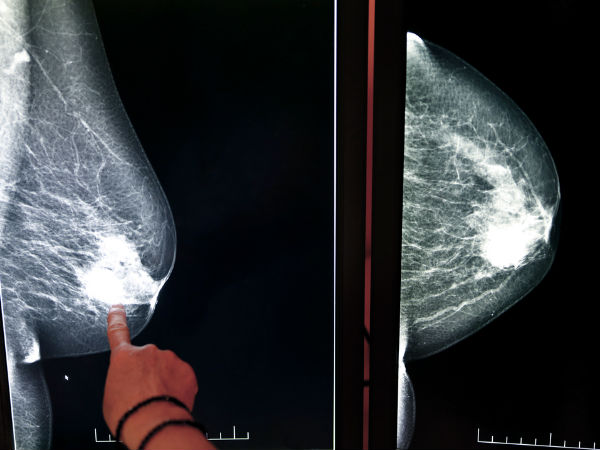

தினமும் வெறும் ஒரு கிளாஸ் ஒயின், பீர் குடித்தாலும், மார்பக புற்றுநோய் வருமாம், ஆய்வில் அதிர்ச்சி தகவல்!

ஆனால், தினமும் ஒரு கிளாஸ் அளவு என பீர் மற்றும் ஒயின் குடித்தால் கூட மார்பக புற்றுநோய் ஏற்படும் அளவு அதிகரிக்கும் என சமீபத்திய ஆய்வு தகவல் வெளியாகியுள்ளது...

அமெரிக்க புற்றுநோய் ஆராய்ச்சி நிறுவனமும், உலக புற்றுநோய் ஆராய்ச்சி நிதி நிறுவனமும் நடத்திய ஆய்வில் வெறும் ஒரு டம்ளர் பீர் அல்லது ஒயின் தினமும் பருகினாலும் மார்பக புற்றுநோய் வரும் வாய்ப்பு இருக்கிறது என கண்டறியப்பட்டுள்ளது.

இந்த ஆய்வில் 12 மில்லியன் பெண்கள் பங்கெடுத்துக் கொண்டனர். அதில் 2.6 லட்சம் பேர் மார்பக புற்றுநோய் தாக்கம் கொண்டிருந்தவர்கள்.

இந்த ஆய்வில் தான் தினமும் ஒரு டம்ளர் பீர், ஒயின் பருகினாலும் மார்பக புற்றுநோய் தாக்கம் உண்டாகும் என ஆராய்ச்சியாளர்கள் கண்டறிந்தனர்.